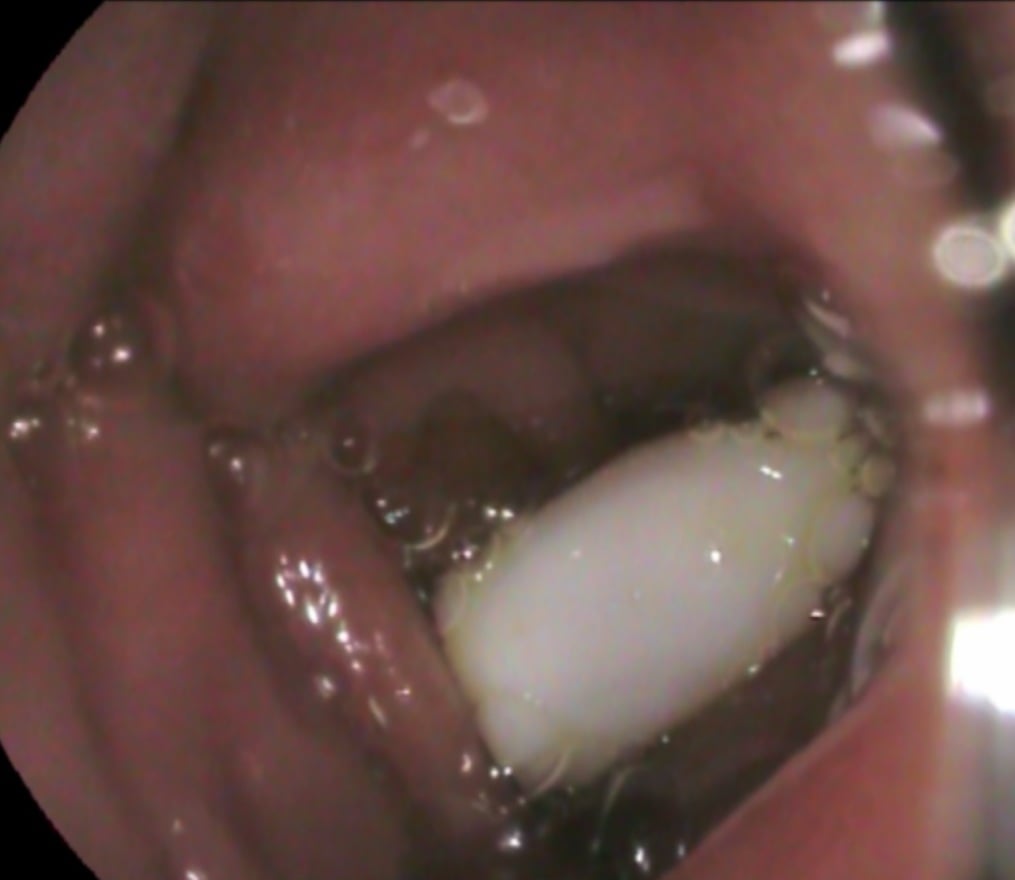

Предмет длиной 6 см оказался аж в двенадцатиперстной кишке. Госпитализированного парня сразу взяли в операционную, где врачи эндоскопически, с помощью специальных устройств, без всякого разреза вытащили распылитель.

Во Львове из горла ребенка достали распылитель от спрея (facebook.com/OHMATDYTLVIV)